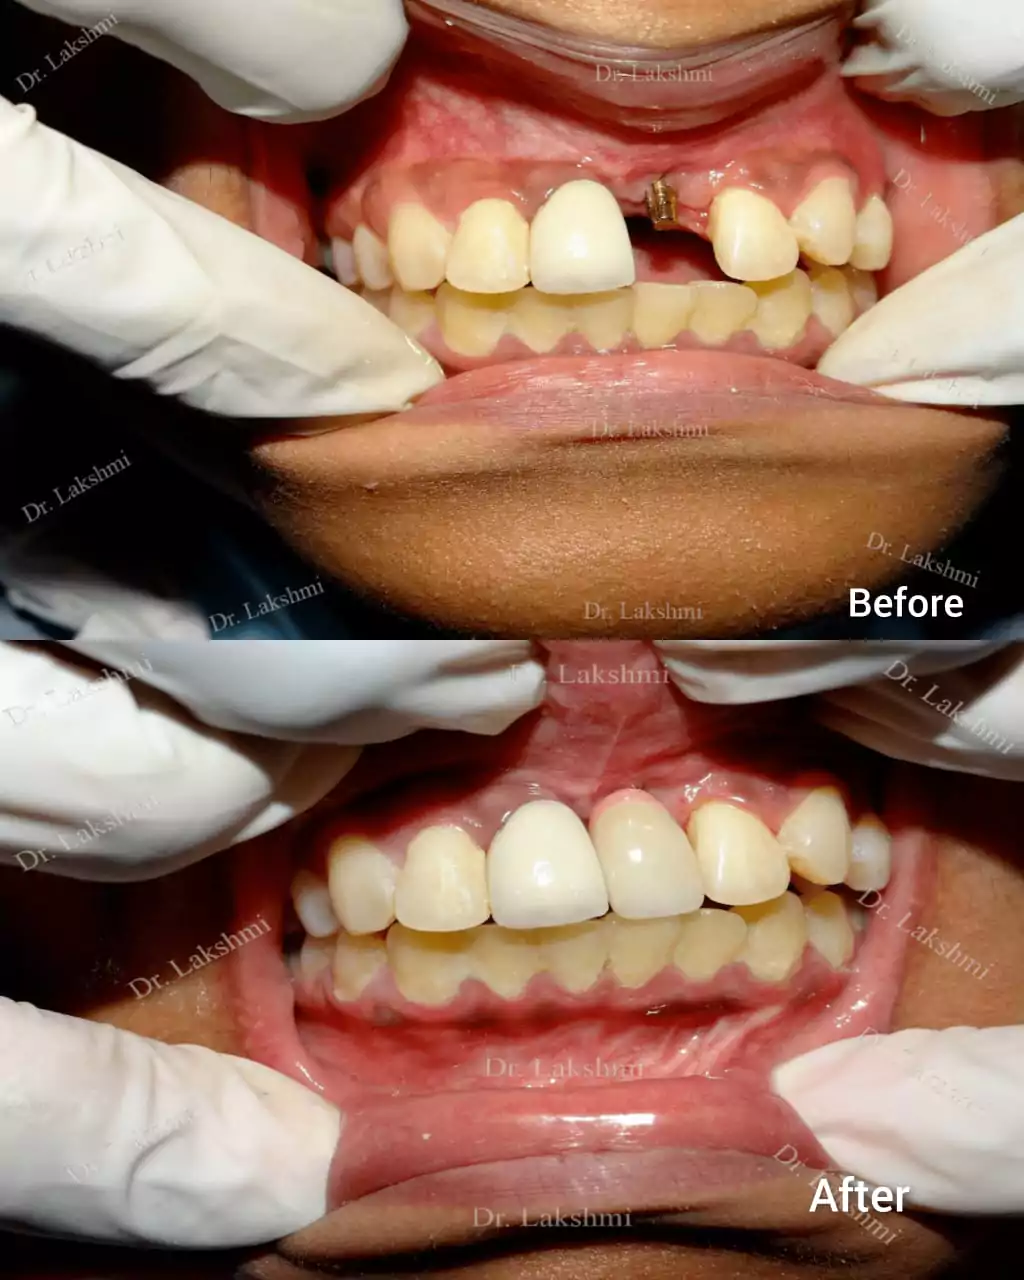

Requires the placement of a single dental implant (either 2 stage or 1 stage) in the region of the missing tooth, followed by a crown (artificial tooth) over

Treatment Duration: 2 stage dental implants: The replacement is completed in 2 stages which are spread over an interval of minimum 3 months. The first stage involves the placement of the implant and requires one to two sittings,Temporary Crowns will be given to the patient. The second stage involves the placement of the artificial tooth (Permanent crown).

1 stage dental implant: Requires just one stage for the placement of the implant and crown(Permanent Crown).